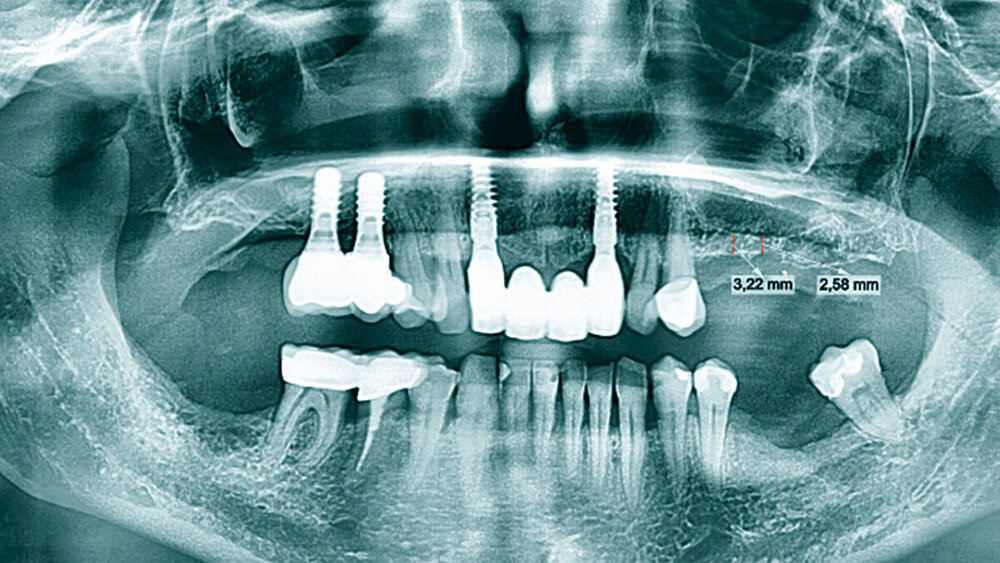

Die anamnestisch unauffällige 56-jährige Patientin erschien auf Überweisung ihres Hauszahnarztes mit dem Wunsch nach festsitzendem Zahnersatz zur Beratung in unserer Praxis. Die Patientin hatte schon vor einigen Jahren mehrere Implantationen in unserer Klinik durchführen lassen und lehnte einen herausnehmbaren Zahnersatz ab. Bei der intraoralen Befundaufnahme zeigte sich ein konservativ und prothetisch suffizient versorgtes Gebiss sowie eine Freiendsituation im zweiten Quadranten mit fehlenden Zähnen Regio 25–28 und eine Schaltlücke in Regio 36. Röntgenologisch konnte im Orthopantomogramm in Regio 25 und 26 eine Restknochenhöhe von 2,5 bis 3 mm festgestellt werden, wodurch ein externer Sinuslift nötig wurde, um die gewünschte Implantatversorgung zu realisieren. Nach ausführlicher Aufwands-, Kosten- und Risikoaufklärung stimmte die Patientin der Behandlung zu.

In den Abbildungen 6 bis 9 sind mehrere Fälle mit langem Beobachtungszeitraum dargestellt. Beachtenswert ist vor allem der zu beobachtende vollständige Umbau des Knochens inklusive der Ausbildung einer neuen Kompakta. Die augmentierten Bereiche sind nach wenigen Jahren nicht mehr als solche zu erkennen. Die Arbeit mit autologem Knochen ist insbesondere für die Patientengruppe interessant, die bevorzugt nach biologisch sicher verträglichen Behandlungen sucht. Dieser Trend nimmt unseren Beobachtungen nach stetig zu. n